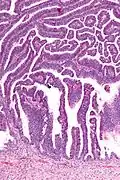

![]() | |

| Micrograph of a villoglandular adenocarcinoma the cervix. H&E stain. | |

The name of the lesion describes it microscopic appearance. It has nipple-like structures with fibrovascular cores (papillae) that are long in relation to their width (villus-like), which are covered with a glandular pseudostratified columnar epithelium.